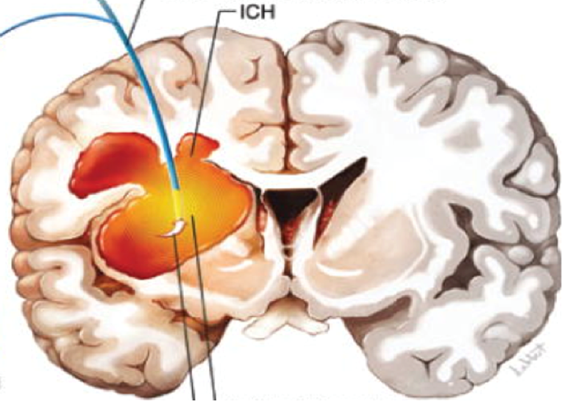

– Cerebral infarction and Cerebral hemorrhage